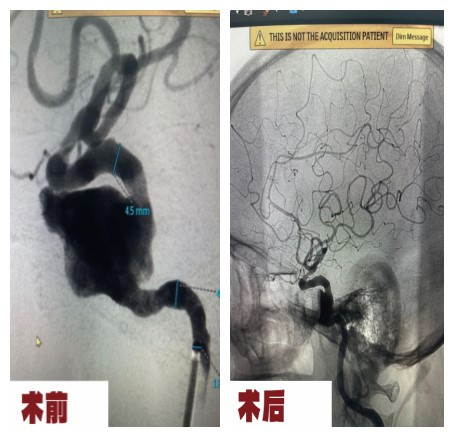

颅内动脉瘤实闭术栓塞术(血流导向装置置入)

颅内复杂动脉瘤包括大型、巨大型、宽颈、梭形、夹层动脉瘤等,是血管内治疗的难点颅内密网支架( 血流导向装置 )通过改变载瘤动脉内的血流方向以减少或减弱动脉瘤内的血流冲击,达到动脉瘤瘤体内血流滞留和血栓形成的目的,最终在支架表面和动脉瘤颈处形成新生内皮细胞,实现动脉瘤的完全闭塞和治愈,与此同时,也实现了载瘤动脉的重建并降低了动脉瘤复发再通的风险。血流导向装置为颅内复杂动脉瘤治疗提供了一个全新理念,治疗重点经历了“瘤内-瘤颈-载瘤动脉”的转变。血流导向装置治疗颅内复杂动脉瘤治愈率高,严重并发症发生率低,是一种治疗颅内复杂动脉瘤的良好方法。我院至2023年独立完成多例高难度复杂颅内动脉瘤血流导向装置置入术,治疗效果良好。